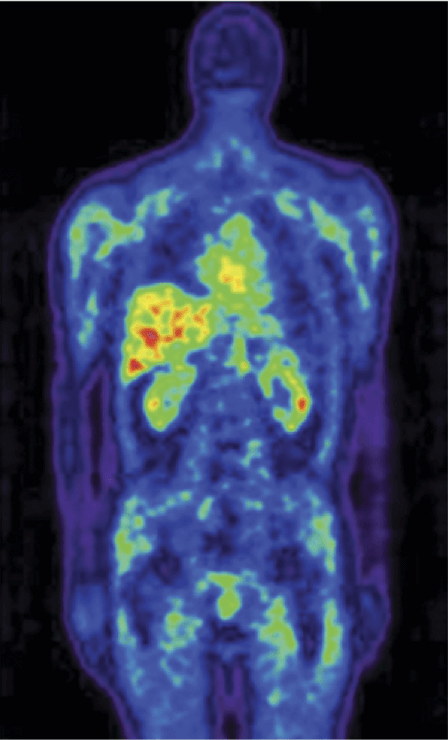

Radio Isotopes Antibody probes